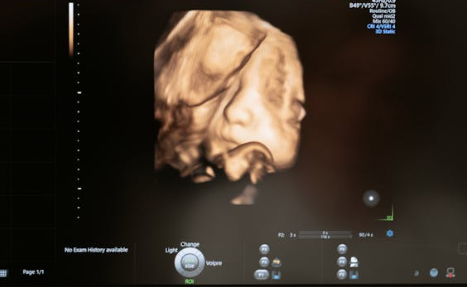

임신 12주 2일차. 초음파실에 들어서는데 괜히 가슴이 두근두근… 💓

아기는 머리부터 엉덩이 길이(CRL) 5.67cm, 목투명대(NT) 1.14mm, 그리고 작은 코뼈(nasal bone)까지 확인할 수 있었어요. 초음파 선생님이 “잘 보이네요”라는 말 한마디를 해주셨을 때, 긴장이 스르르 풀리더라고요.

제 아기는 1.14mm로 같은 주수 평균보다 얇았고, 코뼈도 보여서 안심할 수 있었어요.

검사 전날까지만 해도 불안해서 잠이 안 왔는데, 초음파 속에서 아기가 작은 손발을 움직이는 걸 보자 눈물이 찔끔 났어요.